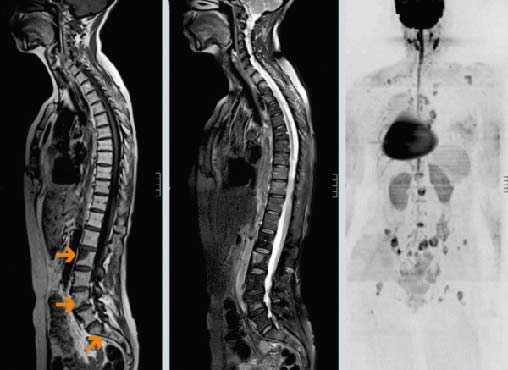

(Слева) На рентгенограмме в бо ковой проекции визуализируется мягкотканная опухоль, замещающая невральную дугу С2. Также определяется деструкция верхнего края боковых масс СЗ. Распространение деструктивных изменений от одной кости к другой нетипично для метастатического поражения.

(Справа) На сагиттальной MPT (Т1 ВИ) у этого же пациента визуализируется крупный очаг в невральной дуге С2. Костный мозг зубовидного отростка замещен опухолью. На рентгенограммах поражение зубовидного отростка выявлено не было - чувствительность МРТ в обнаружении метастазов выше.

о МРТ всего позвоночного столба для обнаружения метастазов в костях, эпидуральных опухолей, сдавления спинного мозга:

- STIR или Т2 WI FS и Т1 ВИ С+ (± FS)